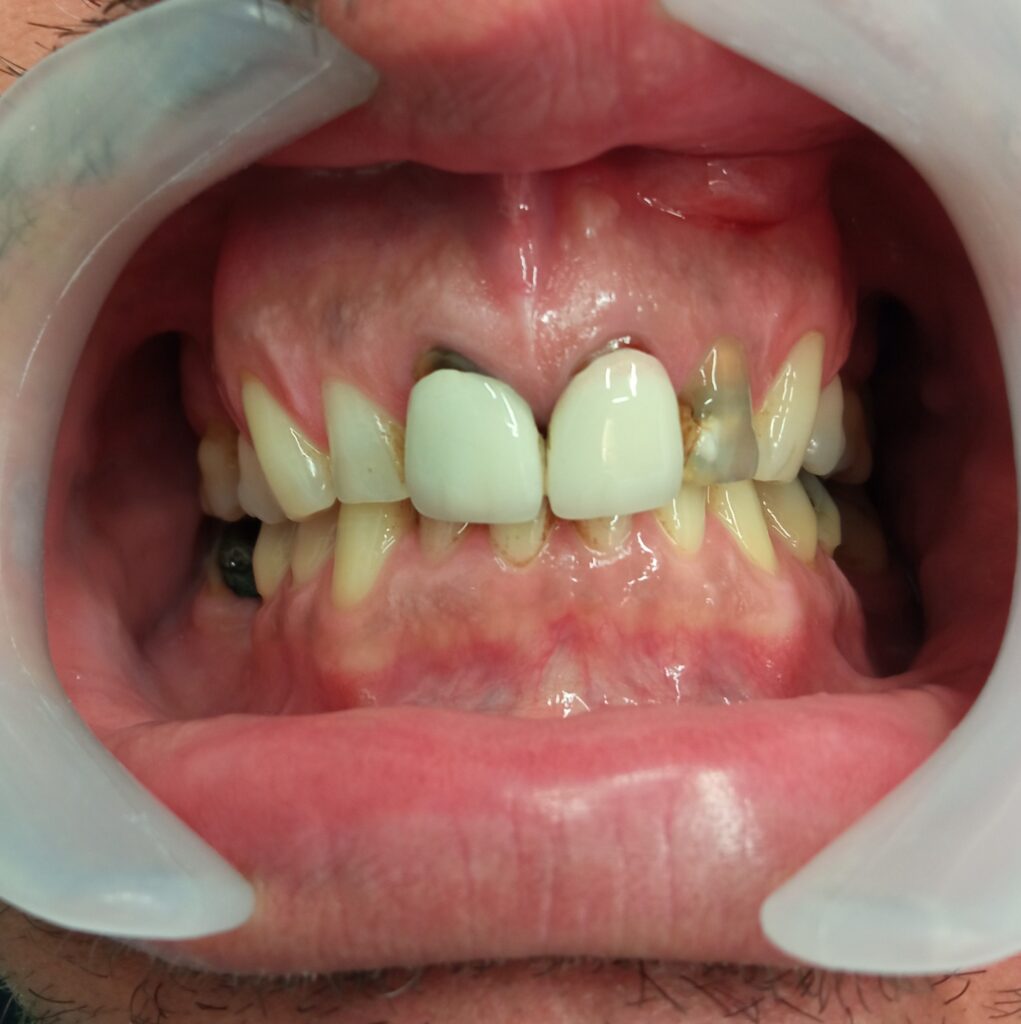

Τα δόντια μετά την αφαίρεση της παλιάς γέφυρας